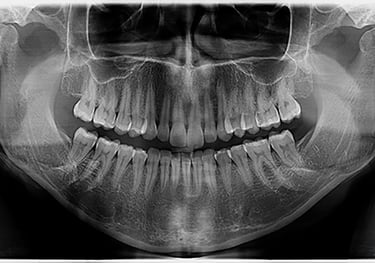

RADIOGRAFIA PANORÂMICA